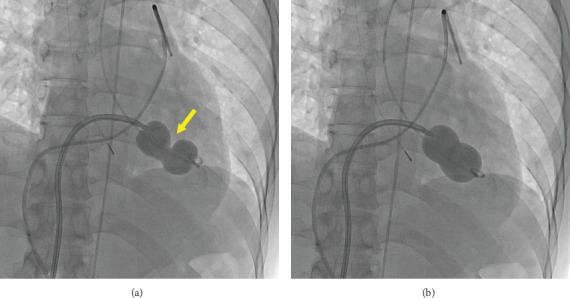

Papillary muscle rupture is a rare but serious complication during percutaneous transvenous mitral commissurotomy (PTMC). In many cases, it leads to acute significant mitral regurgitation (MR), requiring urgent surgical repair. We performed PTMC for a 49-year-old woman with symptomatic moderate rheumatic mitral stenosis. Initial balloon inflation resulted in papillary muscle rupture; however, it did not induce leaflet prolapse and worsening of MR. Finally, we succeeded in achieving a mean pressure gradient of less than 5 mmHg without worsening of MR through several balloon inflations. We experienced a rare case where papillary muscle rupture occurred during PTMC, but there was no development of acute significant MR, and salvage surgery was not required.